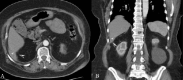

We present a challenging case at our facility involving a 70-year-old female with a history of hypertension who was diagnosed with malignant ovarian neoplasia. Preoperative imaging revealed a 6 x 6 x 2.5 cm mass in liver segment 6, initially suspected to be metastatic disease. The patient had undergone a laparoscopic cholecystectomy 11 years prior. Despite repeated biopsies and a high fluorodeoxy-glucose (FDG) uptake value of 9.87 on positron emission tomography-computed tomography (PET-CT), the exact nature of the mass remained undetermined. However, during a total abdominal hysterectomy and bilateral salpingo-oophorectomy, an excisional biopsy of the liver lesion identified it as an abscess formed around a gallstone, presumably spilled during the previous cholecystectomy. This case highlights a rare but significant diagnostic challenge, wherein a gallstone shed during gallbladder surgery mimicked a metastatic liver mass. It underscores the importance of considering a patient's surgical history in differential diagnoses, especially when encountering atypical abdominal masses.